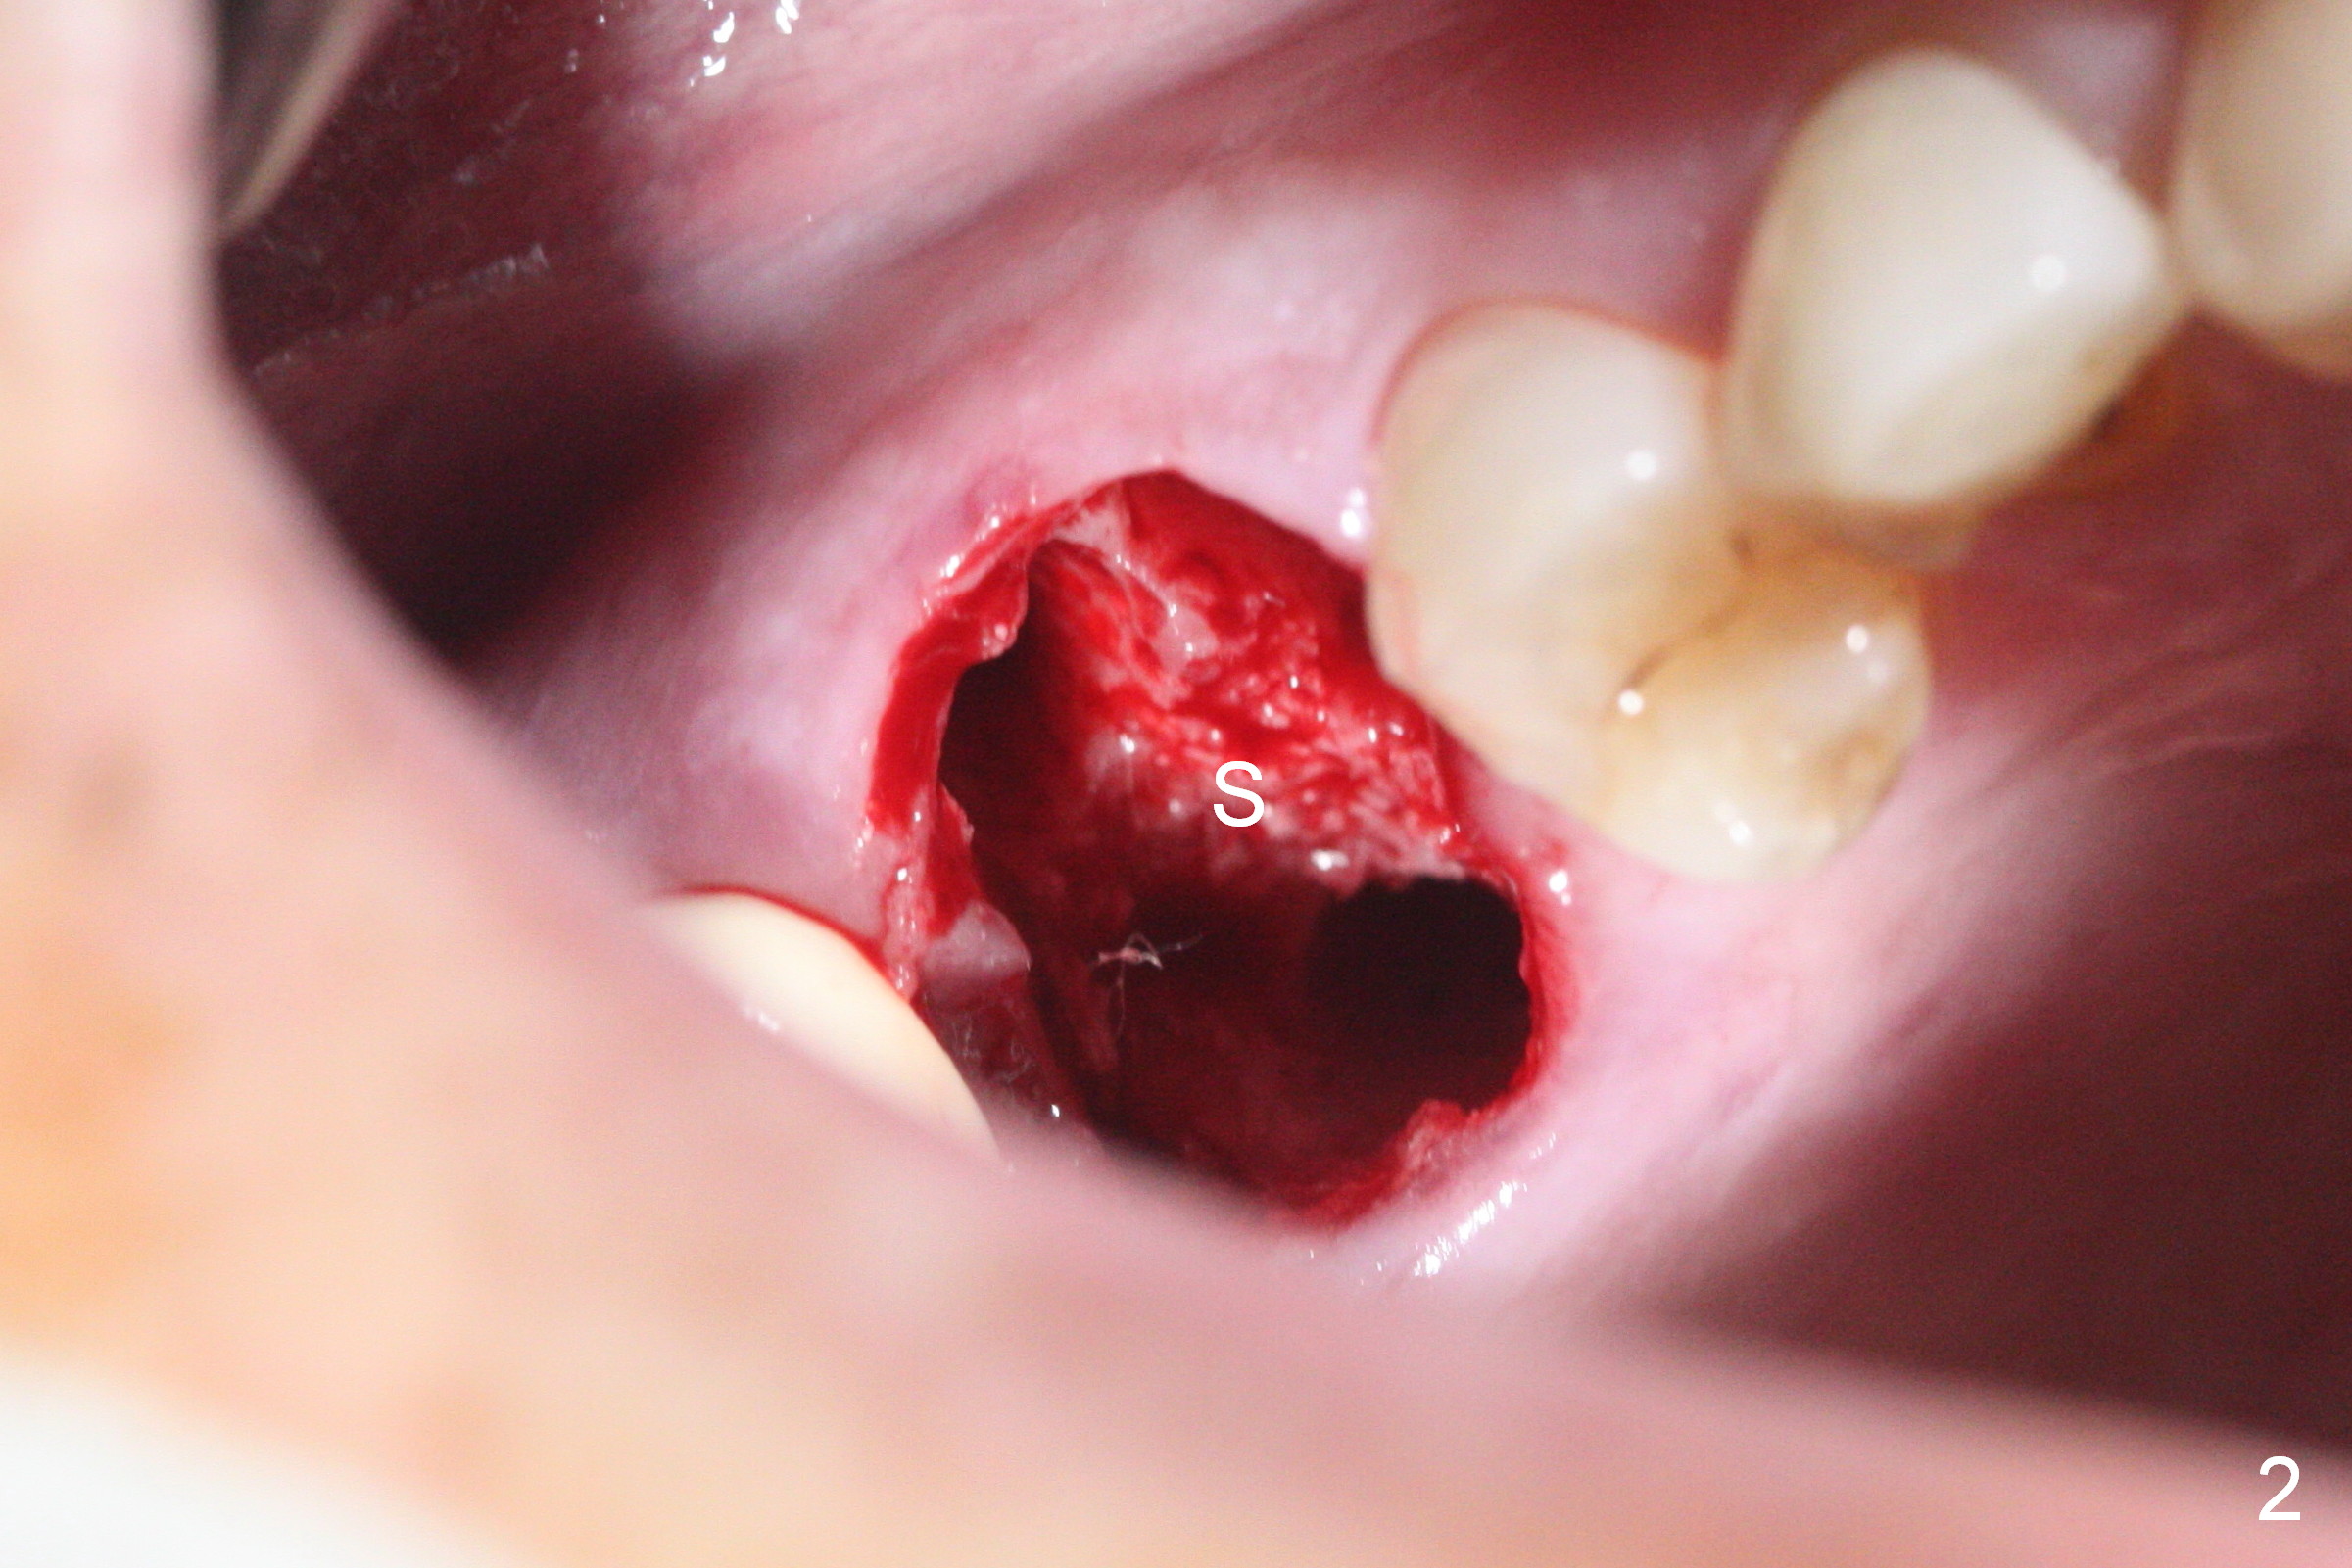

Heavy bruxism is characterized by the crack at #3 (symptomatic, requiring emergency extraction) and loss of the palatal cusp at #5 (Fig.1). Osteotomy is initiated in the septal slope (Fig.2 S) with a 1.6 mm pilot drill for 9 mm (with sudden empty feeling), followed by Marking bur. After 4.3 mm Magic Drill is used for ~ 9 mm, the sinus membrane is found to perforate. A dummy implant (5x9 mm, 2 mm shorter than design) is placed short of the sinus floor (Fig.3 ^). Prior to placement of 5.5x9 mm IBS implant (~ 35 Ncm, Fig.4,5), a piece of Osteogen plug is inserted into the osteotomy for repair of the perforation. The final implant is also shy of the sinus floor (Fig.5 ^). The Osteogen plug is apparently placed underneath the sinus floor so that it should be able to repair hard and soft tissue defects. The remaining sockets are mainly filled with Osteogen plug, while the implant plateau is covered by autogenous bone and Osteogen. When a 6.5x4(3) mm abutment is placed, an immediate provisional is fabricated (Fig.6) with its margin placed subgingival (Fig.6 inset dashed line). This innovative design of the provisional is to prevent collapse of the most coronal gingiva and loss of bone graft, particularly where the bony plate is defective. Although there is mild pain postop, nasal hemorrhage or discharge is absent.